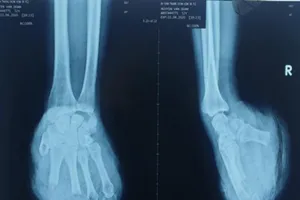

7 giờ căng thẳng nối bàn tay đứt lìa phức tạp